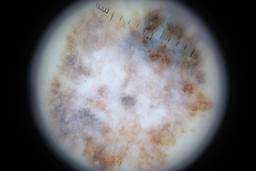

{

"age_approx": 65,

"anatom_site_general": "anterior torso",

"concomitant_biopsy": true,

"dermoscopic_type": "non-contact polarized",

"diagnosis_1": "Malignant",

"diagnosis_2": "Malignant melanocytic proliferations (Melanoma)",

"diagnosis_3": "Melanoma in situ",

"diagnosis_confirm_type": "histopathology",

"family_hx_mm": false,

"image_type": "dermoscopic",

"mel_thick_mm": "0.00",

"melanocytic": true,

"patient_id": "IP_4465811",

"personal_hx_mm": true,

"sex": "male"

}